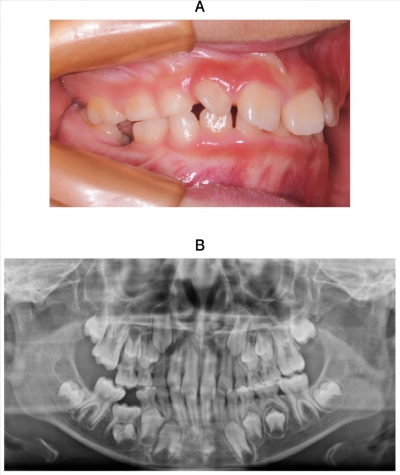

9歳の男児。右側臼歯部の咀嚼困難を主訴として来院した。検査の結果、まず上顎右側第一大臼歯の開窓を行うこととした。初診時の口腔内写真とエックス線写真を示す。

次に行うのはどれか。1つ選べ。

a. 下顎右側第一乳臼歯の形態修正

b. 下顎右側第一乳臼歯の抜去

c. 下顎右側第二乳臼歯の牽引

d. 上顎右側第二乳臼歯の抜去

e. 下顎右側第一大臼歯の整直